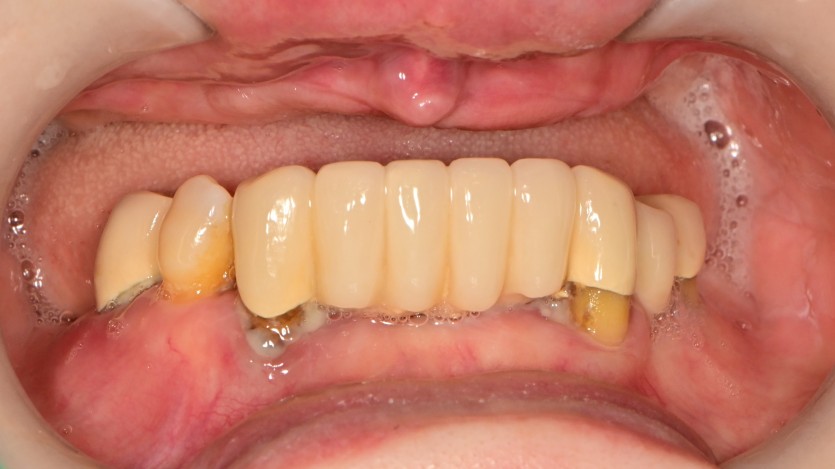

전체 임플란트 증례입니다.

16개의 임플란트로 완성하였습니다.